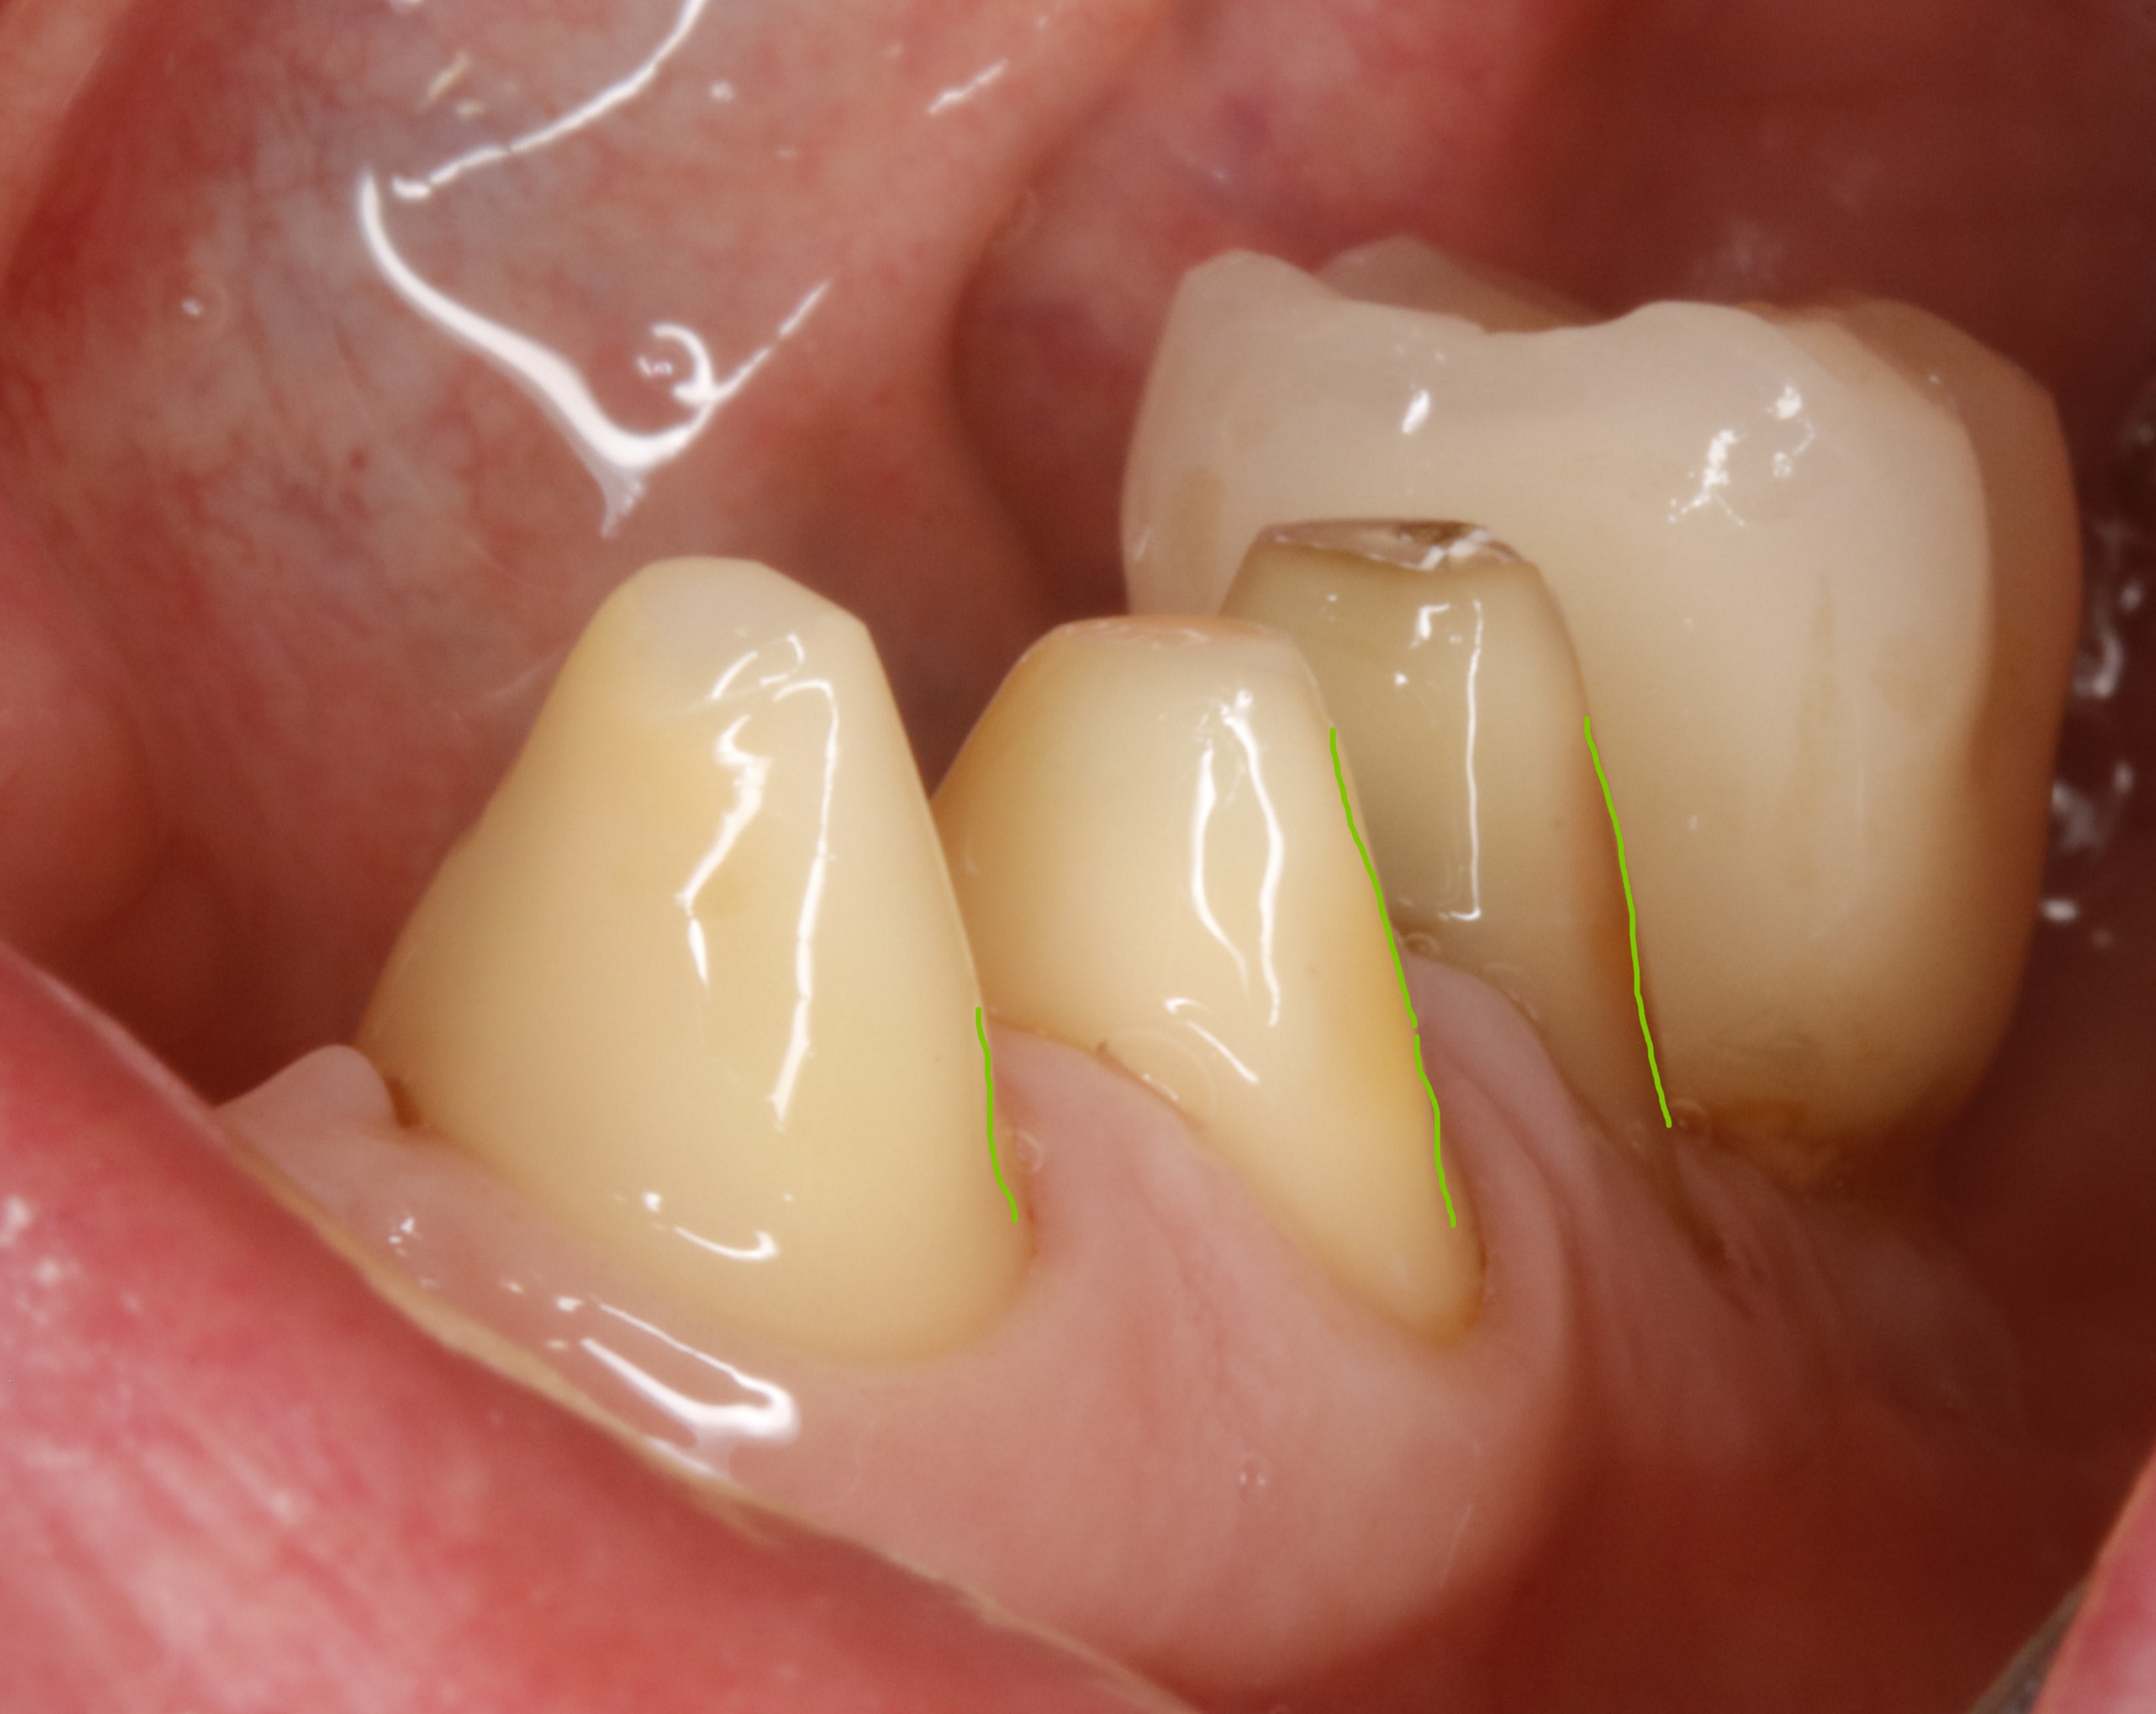

Daryl on va parler de la conicité , et tu vas voir qu ici par exemple eh bien ce n est pas si conique que ça , c est d'ailleurs pour ça que le prov tient tout seul.

la conicité vient toute seule , ce n est pas toi qui la détermine , c est la fraise et le cas prothétique .

la conicité tu la subis et faut jouer avec .

ici , on doit faire un bridge canine canine .les autres dents sont juste des piliers accessoires .

les canines etant les plus costaudes , on va donc essayer de ne pas trop les fracasser et les choisir comme axe d insertion . ce sera donc notre axe de taille directeur . cet axe etant bien sur l axe moyen (ou commun) entre les deux .

donc on commence par tailler les canines en mettant de dépouille .

alors maintenant derrière c est diffèrent , avec la langue , ce n est pas du tout auto stable , et vu que devant c est assez incliné , il va falloir trouver de la rétention . et y en a pas beaucoup et elle se trouve juste au depart de la dent . elle est si précieuse qu une fois taillée , on y reviendra plus jamais .

ce sera notre axe de rétention de référence pour tout le bridge .

et on ne peut pas dire qu il y ait de la conicité entre les deux .

voir les traits bleus sur la photo , sauf si comme dans mission impossible , elle disparait .:-)

donc on les parallélise aux canines sur les faces vest .

traits verts sur photo